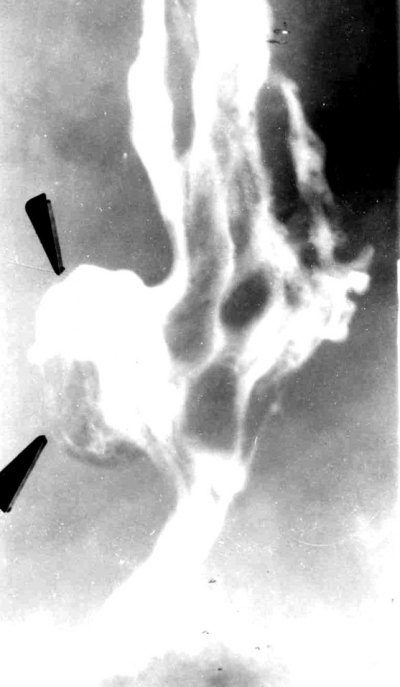

סעיף אמצע וושטי - Midthoracic diverticulum

סעיף זה הוא נדיר. לרוב הוא אמיתי, ורק לעתים נדירות הוא גורם לסימנים קליניים. ברוב החולים הוא נובע מהידבקויות של בלוטות הלימפה לוושט וממשיכת דופן הוושט. הרקע להגדלת הבלוטות הוא מחלות גרנולומטוטיות של הבלוטות (תצלומים 5.1 ו-6.1).